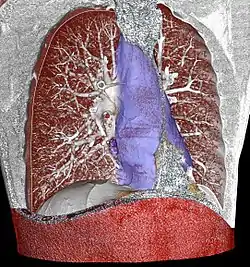

![]() Mediastinum. The division between superior and inferior is at the sternal angle. | |

The mediastinum can be divided into an upper (or superior) and lower (or inferior) part:

- The superior mediastinum starts at the superior thoracic aperture and ends at the thoracic plane.

- The inferior mediastinum from this level to the diaphragm. This lower part is subdivided into three regions, all relative to the pericardium – the anterior mediastinum being in front of the pericardium, the middle mediastinum contains the pericardium and its contents, and the posterior mediastinum being behind the pericardium.[6]